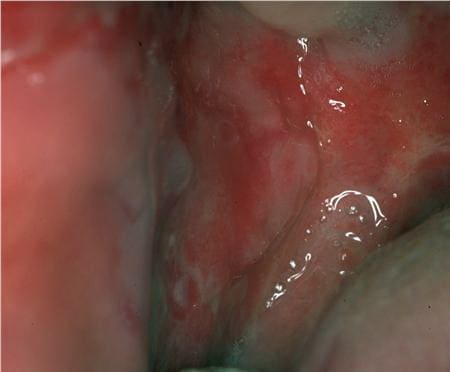

Pemphigus Mucosae = فقاع الاغشية المخاطية